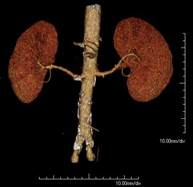

Prova diagnòstica que consisteix en obtenir imatges bi i tridimensionals del ronyó i del sistema urinari d'alta definició anatòmica mitjançant l'ús d'un equip de TC (Tomografia Computeritzada). Es realitza l'estudi abans i després de l'ús de contrast iodat en diferents "fases renals" per a una valoració funcional i anatòmica: parènquima renal, urèters, bufeta urinària, artèries i venes renals, etc. així com les estructures adjacents (vena cava inferior, aorta abdominal, fetge, melsa, etc.). Està especialment indicat quan hi ha sospita de lesions renals, en pacients amb sang a l'orina o hematúria, etc. - TC Urològic

Prova diagnòstica no invasiva que consisteix en l'estudi de les artèries renals a través de l'obtenció d'imatges d'alta definició anatòmica mitjançant l'ús d'un equip de TC (Tomografia Computeritzada) i de contrast iodat. La qualitat de les imatges permet realitzar reconstruccions en 2D i 3D gràcies a estacions de treball especialitzades en l'estudi arterial. Està indicat en aquells pacients amb malaltia vascular (arteriosclerosi), en aneurismes d'aorta, en pacients amb dolor abdominal de possible origen vascular, en estudis prequirúrgics de lesions adjacents a l'aorta abdominal com a "mapa" vascular. La informació obtinguda de manera no invasiva és indispensable per als pacients que requereixen tractament percutani o quirúrgic. En aquells pacients que només requereixen seguiment de les lesions vasculars, aquesta tècnica és la tècnica no invasiva d'elecció juntament amb l'angio-RM. - Angio-TC Aorto-ilíac

Prova diagnòstica no invasiva que consisteix en l'estudi de les artèries renals amb l'obtenció d'imatges d'alta definició anatòmica mitjançant l'ús d'un equip de TC (Tomografia Computaritzada) i contrast iodat. La qualitat de les imatges permet realitzar reconstruccions en 2D i 3D gràcies a estacions de treball especialitzades en l'estudi arterial. Aquesta prova està indicat en aquells pacients que pateixen HTA refractària al tractament, en pacients amb lesions renals que tenen un mapa vascular prequirúrgic, etc. - Angio TC d'aorta-ilíaca